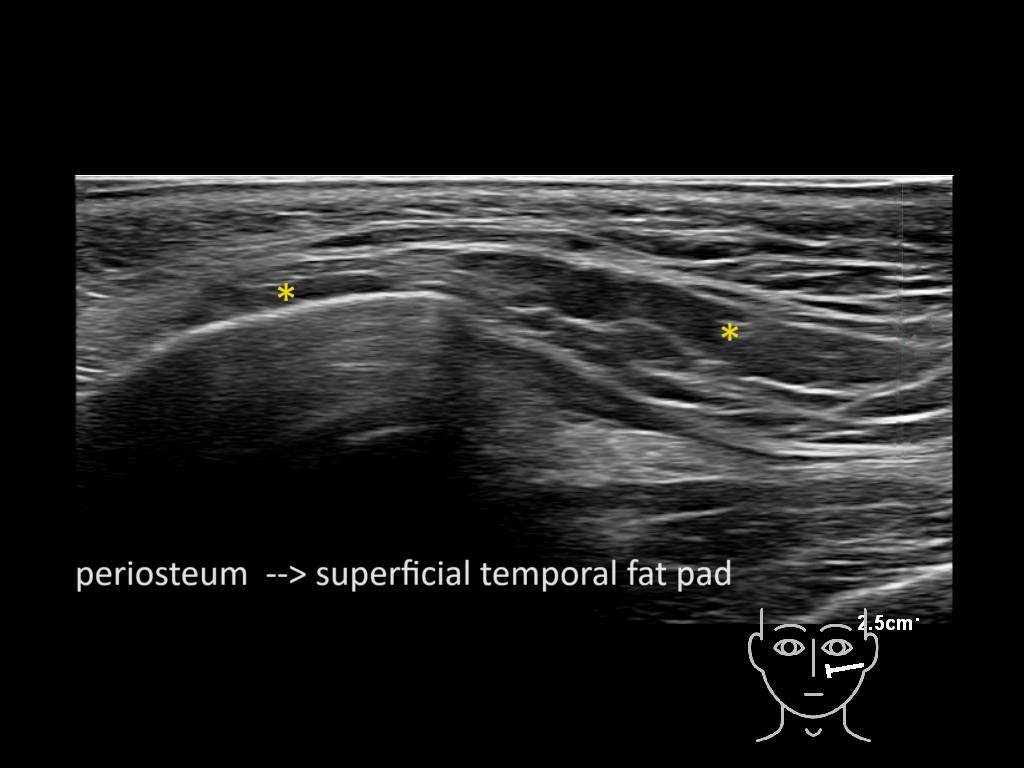

Filler behavior - Temple zygoma US

Study the first image to recognize the different layers. If you are sure about the layers, swipe to the second image to view the answer (if applicable).